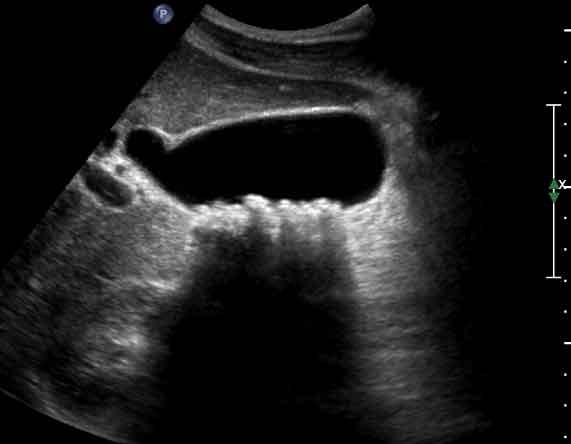

담석증 검사-복부 초음파 검사-담석은 CT나 X레이로도 확인하기 어려운 경우가 많으며, 1차 검사는 복부 초음파 검사입니다.

담석의 복부 에코 영상 초음파 소견에서 간과해서는 안 될 것은 음향 그림자(acoustic shadow)입니다.